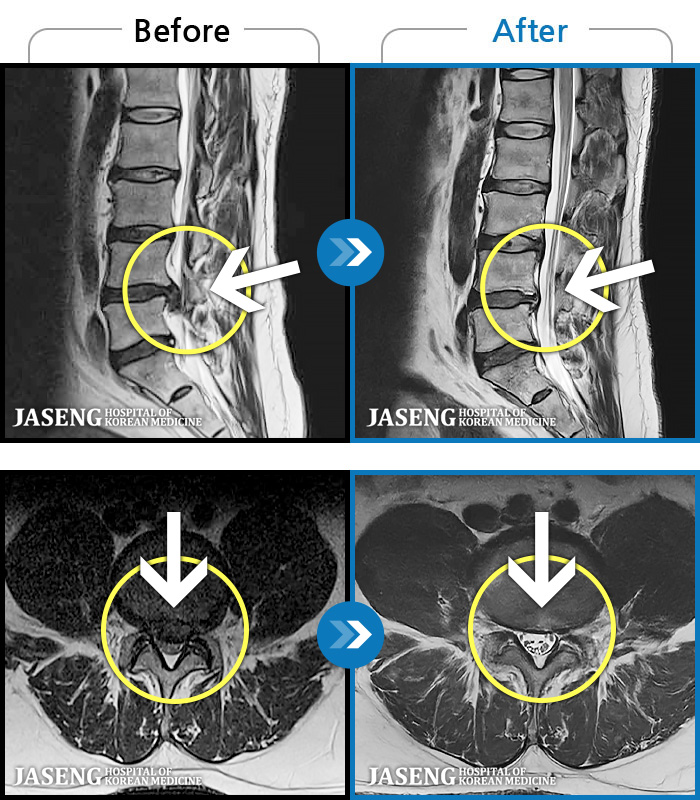

[] 03.04.01~09.11.01